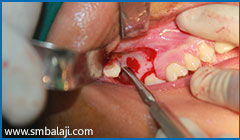

Surgical exposure of lower right impacted teeth

Surgical exposure of lower left impacted teeth